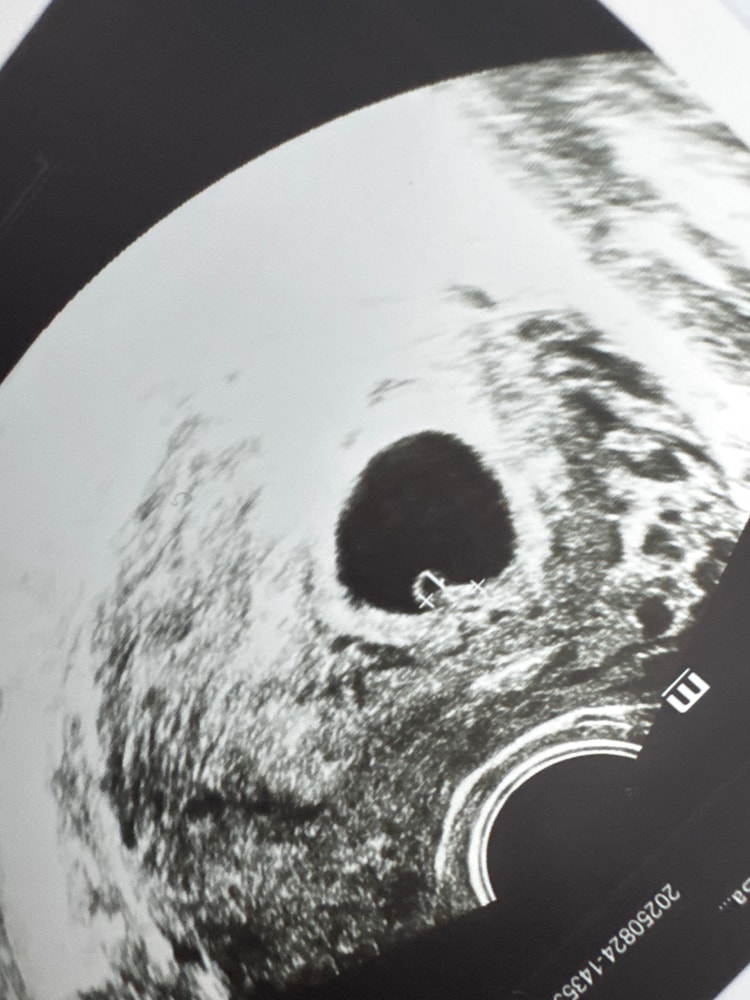

Выделения обычные светло желтые , но их как будто стало больше. И при этом ноет живот , но у меня жесткие запоры, поэтому возможно это кишечник. А может нет. По узи 11.09 была гематома 1х1см

сейчас срок 11н

Сейчас 10н5д , по самочувствию уже лучше становится. Тошнота вроде как прошла, начался жор😂 грудь также чувствительна . Постоянно мерзну. Вроде как сонливость уже не такая сильная. В 9н нашли гематому 1х1 , но она мне не мешает. Больше всего мне мешает мой кишечник, начались лютые запоры🫤🫤На скрининг записалась в 13.0 через пару недель. Сердечко

10 дней назад жм был 3мм(в 6н)

сегодня ктр 13мм, ПЯ 32мм, жм 5мм

большой ?